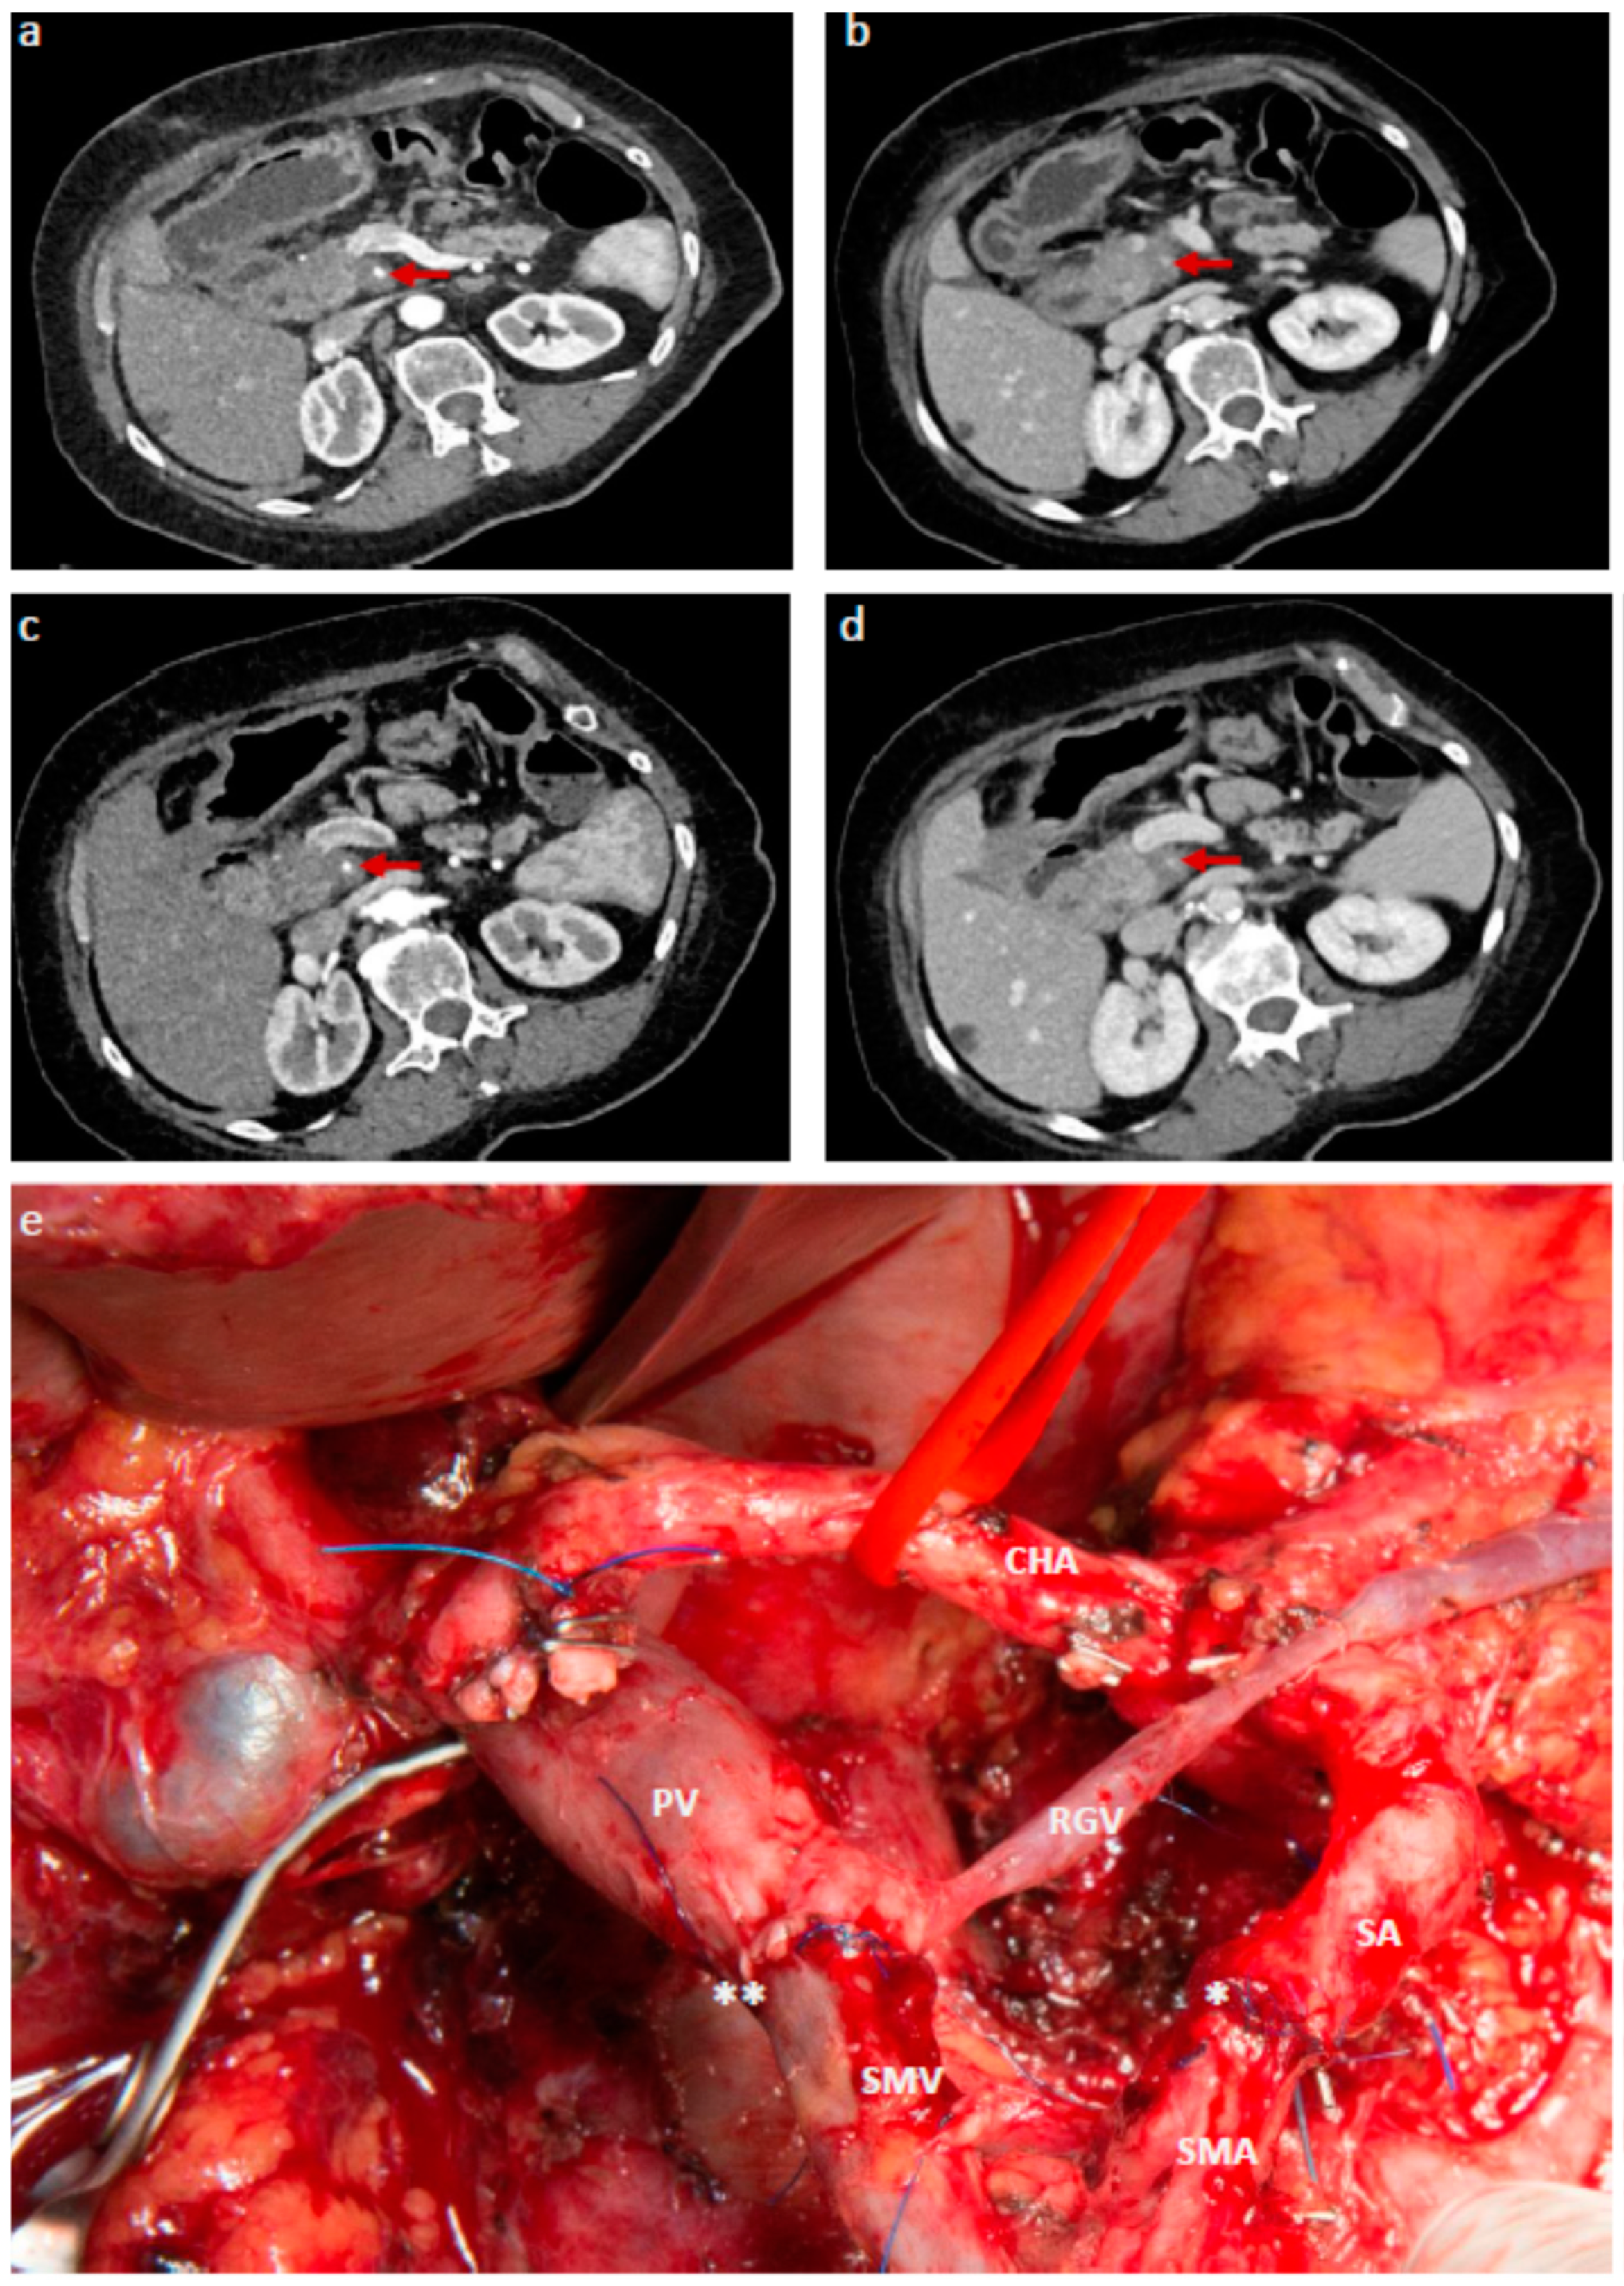

- Hackert, T.; Strobel, O.; Michalski, C.W.; Mihaljevic, A.L.; Mehrabi, A.; Muller-Stich, B.; Berchtold, C.; Ulrich, A.; Buchler, M.W. The triangle operation-radical surgery after neoadjuvant treatment for advanced pancreatic cancer: A single arm observational study. HPB 2017, 19, 1001–1007. [Google Scholar] [CrossRef] [PubMed]